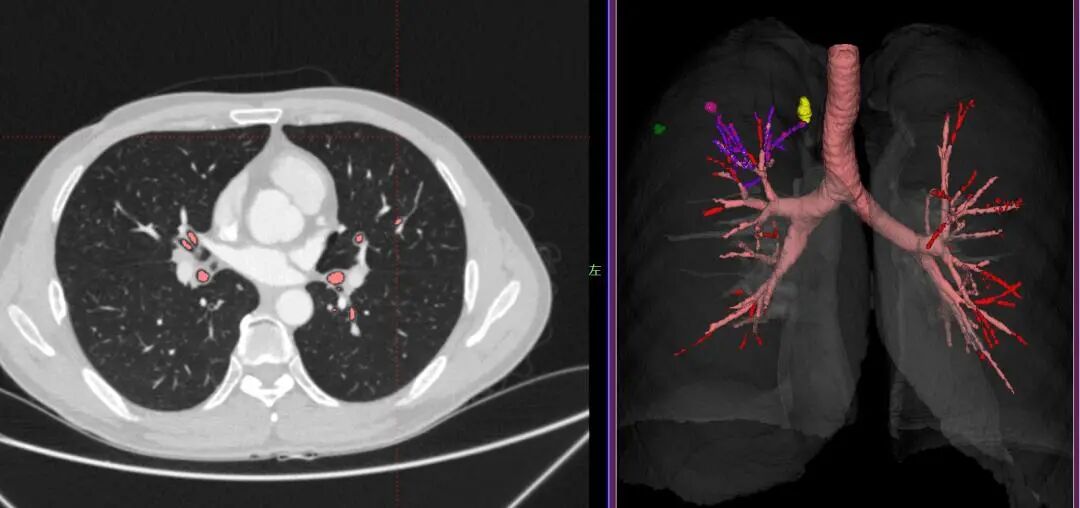

今天给大家介绍一下电磁导航支气管镜,磁导航就好比“GPS”,能精准定位肺结节的位置,目前已在临床上应用于手术当中。 电磁导航支气管镜其实就是我们熟知的支气管镜加了“GPS”定位系统,这样就可以更加准确快速抵达病变的区域,进行组织活检或者治疗了。 而且支气管分支越往下越细,对于生长在肺周围的病灶,普通支气管镜“鞭长莫及”,很难抵达;细支气管镜虽然可以抵达病灶,但是要花很长时间去寻找合适路径。 而电磁导航支气管镜就解决了这样的难题,支气管镜的探头可以根据磁导航迅速到达病变部位,就像在GPS定位下开车一样,安全高效。   从气管进入,无需穿刺,副作用和风险较小。 它不仅可以轻松取活检,帮助诊断小结节的性质,还能辅助其他治疗。   比如对于身体不适宜进行手术的病人,就可以直接用电磁导航支气管镜进行其他微创治疗,如射频消融治疗(射频电流直接加温到肿瘤局部,使肿瘤热凝固坏死)等,从而实现“不开刀治肺癌”的目的,减少对患者造成的痛苦和身体上的伤害。